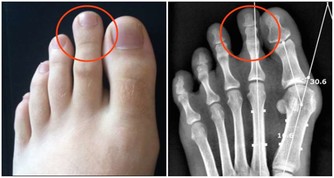

·腿部或腳部腫脹;

·背部疼痛,位置在腰部以上(腎臟位置);